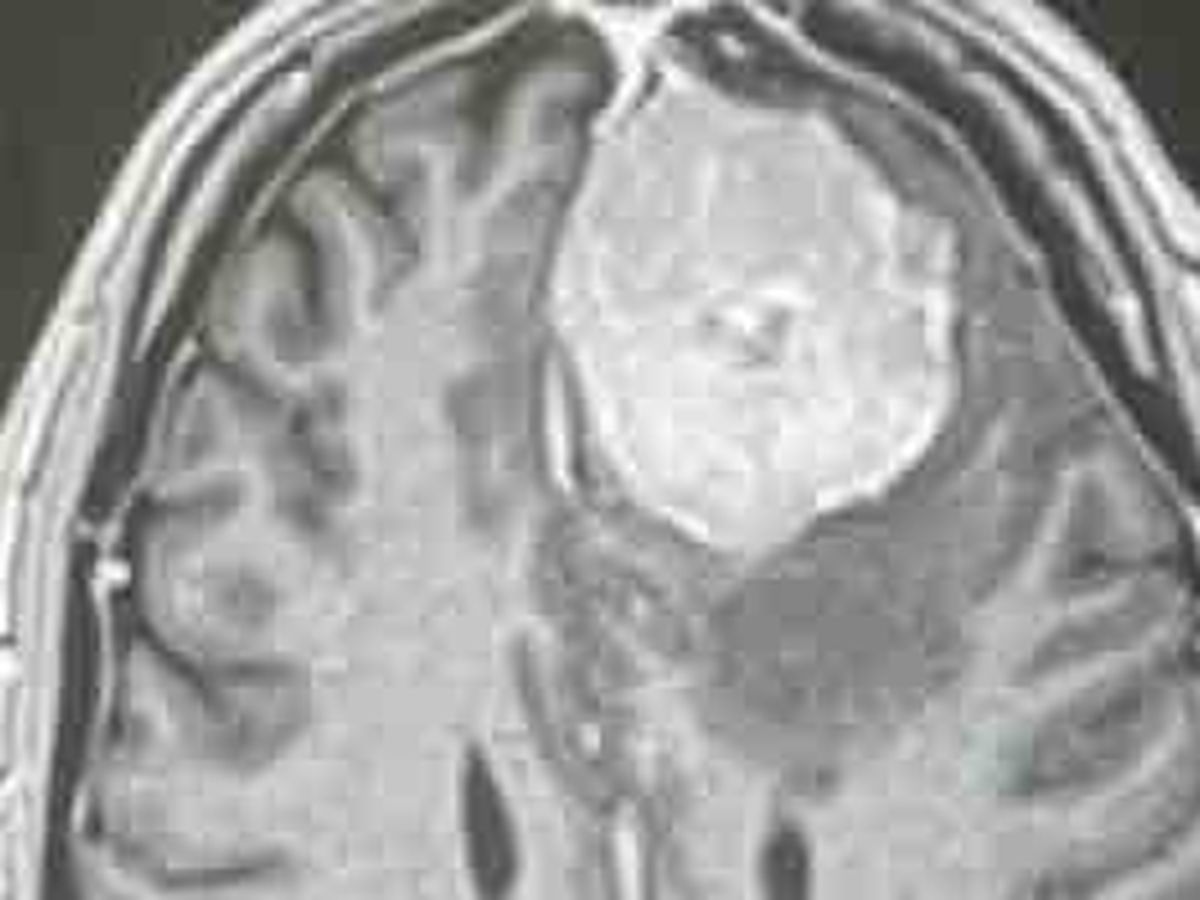

Once in the hospital I was given an MRI where

the neurological team fond a 5x4x4 cm tumor growing inside my left frontal lobe with current blood flow.

The pressure has been extensive and is around 15-20 years old according to the bruised aera and size on the scan.

The mass is not cosmetic or something that can be left untreated. It must have action taken now for my health. .

I have a tumor the size of a small lime to a tennis ball pressing on my left frontal lobe that must come out and I need some confidence it will come out.